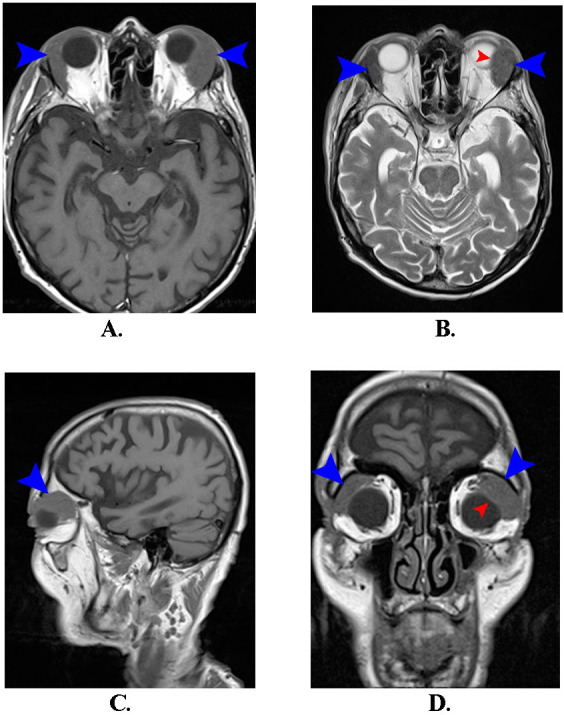

Lacrimal gland lymphomas are rare orbital tumors, constituting a minor fraction of all orbital and ocular adnexal malignancies. This case study presents an 83-year-old male with bilateral lacrimal gland tumors, more prominent in the left orbit, causing decreased visual acuity, red eye, excessive tearing, and diplopia. Initial ophthalmological evaluations and imaging suggested bilateral lacrimal gland lymphoma, confirmed by histopathology as diffuse large B-cell non-Hodgkin lymphoma of the MALT type. Due to the significant tumor size and risk of visual function loss, surgical intervention was performed, followed by corticosteroid therapy. Postoperatively, a marked improvement in symptoms and a reduction in tumor size were observed. This case underscores the importance of comprehensive diagnostic approaches, including clinical, imaging, and histopathological evaluations, highlighting the need for a multidisciplinary approach in managing rare orbital tumors like lacrimal gland lymphoma. The patient's postoperative and follow-up care included oncological management to monitor and ensure long-term disease control and patient well-being. Abbreviations: RE = right eye, LE = left eye, CT = Computer tomography, MRI = Magnetic Resonance Imaging, TOD = intraocular pressure of right eye, TOS = intraocular pressure of left eye, US = ultrasound.